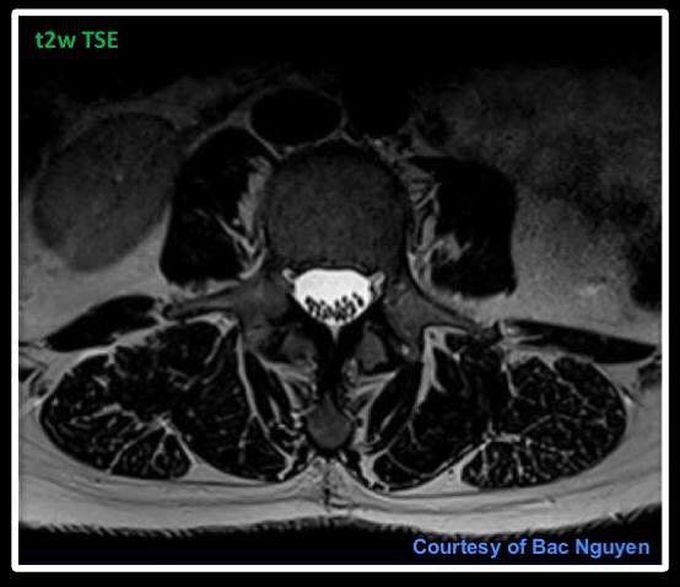

Lumbar Spine Imaging – transversal @ Siemens 3T Skyra I just wonder what phase direction you tend to use on these transversal slices, Right – Left or Anterior – Posterior? This transversal showing here was acquired with a phase direction of Right – Left.#s_mri #mri #siemens #lumbarspine